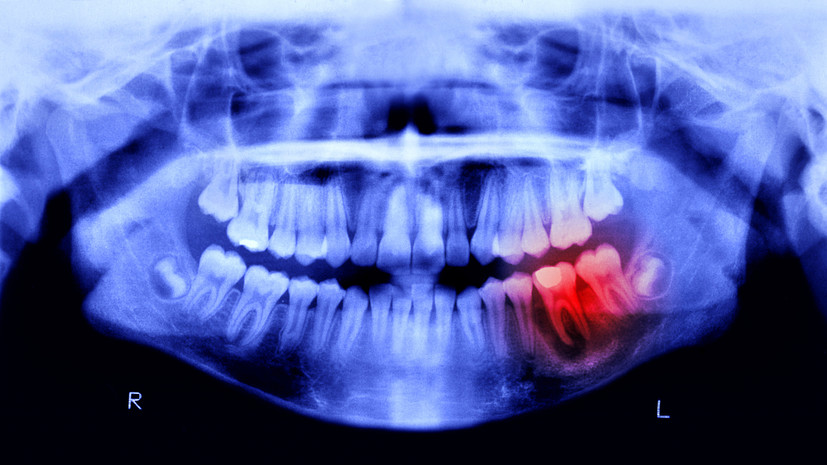

Ведущий стоматолог Виктория Шелудкова объяснила, почему важно не игнорировать первые признаки кариеса. По её словам, разрушение эмали из-за этой болезни — главный провокатор дискомфорта.

Специалист подчеркнула: если вовремя не начать лечение, боль станет постоянной, особенно ночью.

«На поздних стадиях патологии активно задействуется блуждающий нерв, что многократно усиливает неприятные ощущения, — отмечает Шелудкова. — К сожалению, таблетки уже не спасут, так как воспаление достигает пульпы».